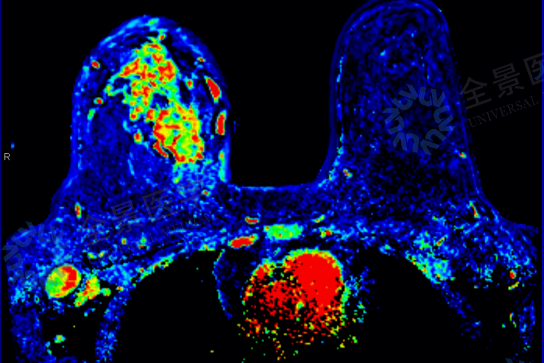

从「结节 4A 类」到「炎性乳腺癌」:一次深度筛查,改写她的生命轨迹